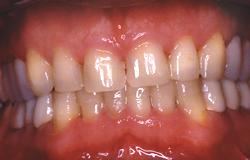

Nouvelle DVO. Augmentation de 6 mm par rapport à la situation d'origine.

Idéalement, la longueur de l'incisive centrale doit être de 11 mm.

Le patient est laissé dans cette situation pendant 1 mois afin de vérifier qu'aucun trouble ne réapparaît.